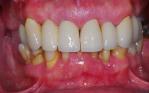

Full mouth implant reconstruction with an upper full arch zirconia bridge supported on six implant fixtures, and a lower full arch titanium framework acrylic bridge, also on six implant fixtures.

Before

After